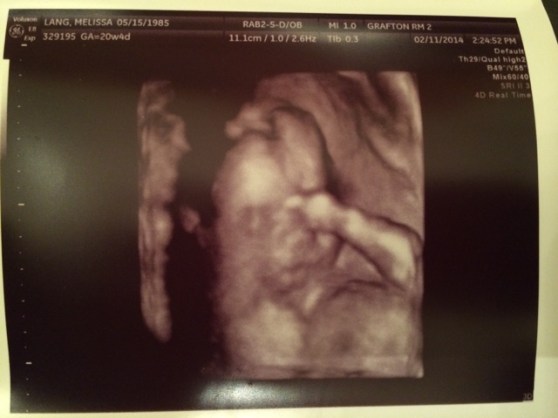

3D Ultrasound Face Pic! This one is my second fave. Smooshy pout face.

My favorite little face pic. She’s just so precious with her little hand up by her face. I can’t wait to kiss that little face.